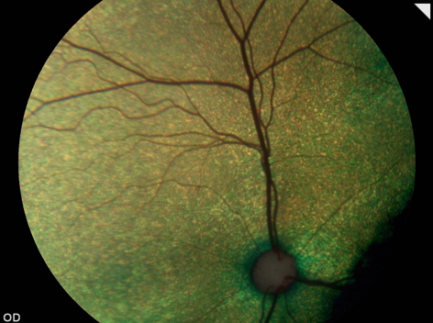

Una retinografía es un procedimiento diagnóstico que nos permite, a modo de fotografía, obtener imágenes en color de la retina. Es una prueba que proporciona una información muy valiosa sobre el estado de la retina y el nervio óptico.

La retinografía es una herramienta fundamental en la detección precoz y el seguimiento de determinadas patologías relacionadas con el nervio óptico (hipoplasia, coloboma, neuritis, …), la retina (degeneraciones, desprendimiento retina, procesos inflamatorios, hemorragias …) y para detectar alteraciones vítreas tales como hemorragias y degeneraciones.